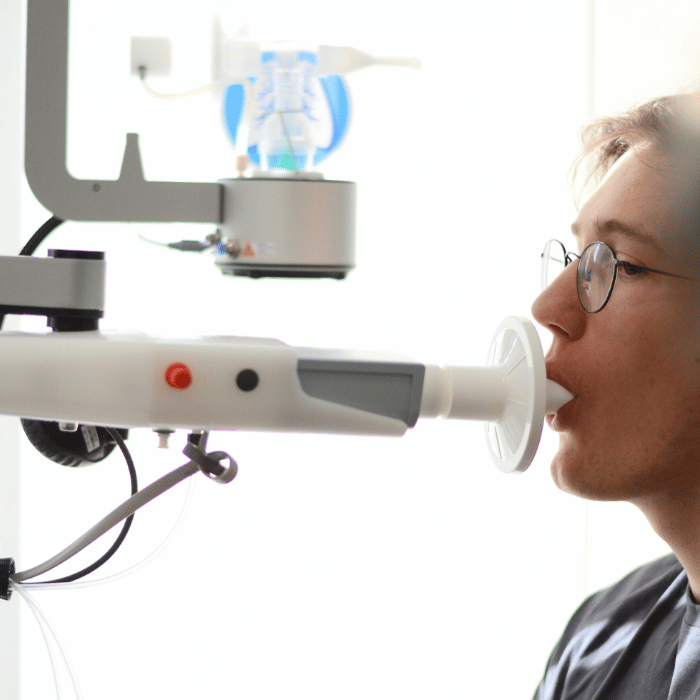

Sorgfältige Abklärung

– moderne Diagnostik

Jede Untersuchung beginnt mit einem ausführlichen Gespräch und wird individuell auf Ihre Situation abgestimmt. Moderne Diagnostik ermöglicht es, Erkrankungen frühzeitig zu erkennen und Therapien präzise auszurichten.

Hier finden Sie einen Überblick über meine verschiedene Leistungen.